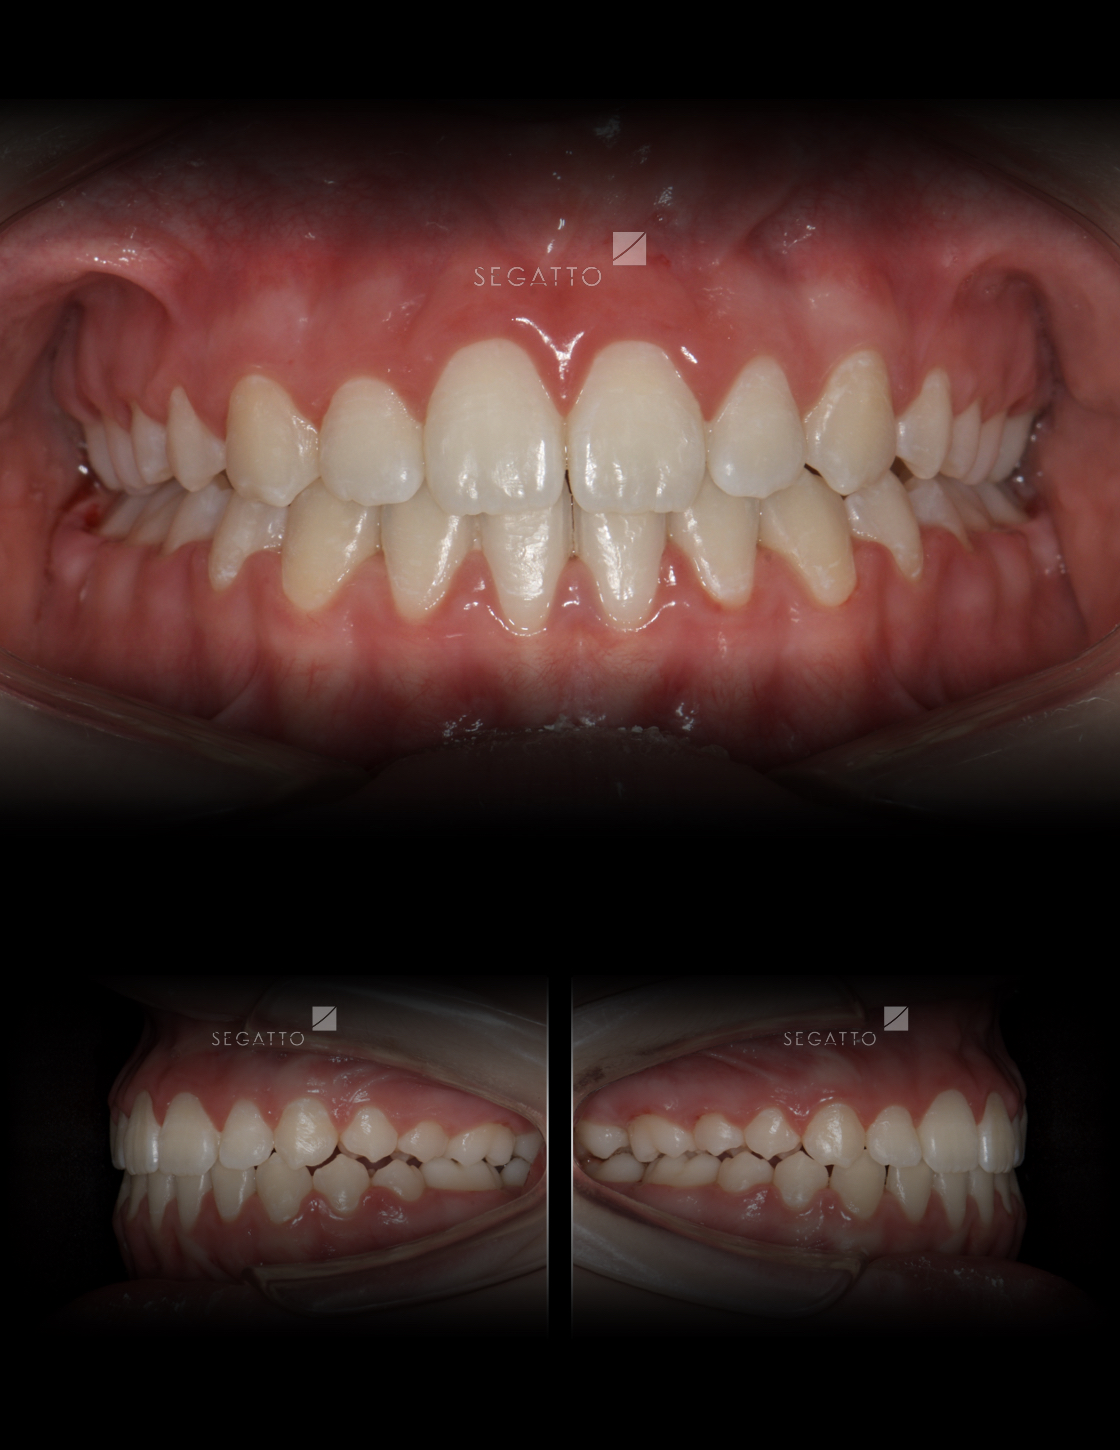

Orthodontics

Cases